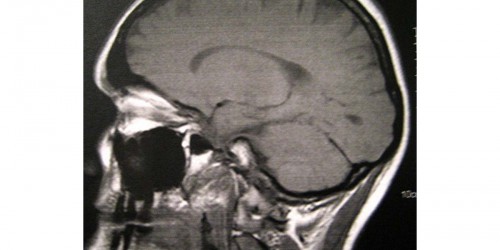

My son was diagnosed when he was 18 with nf2 she's had five brain surgeries he's had the one on the right Temple removes had one on the left temple removed with a cyst he also had both bone plots removed and a tumor behind the eye removed he still has numerous numerous tumors he has one on acoustic nerve that are growing quite large how long do you think he has to live